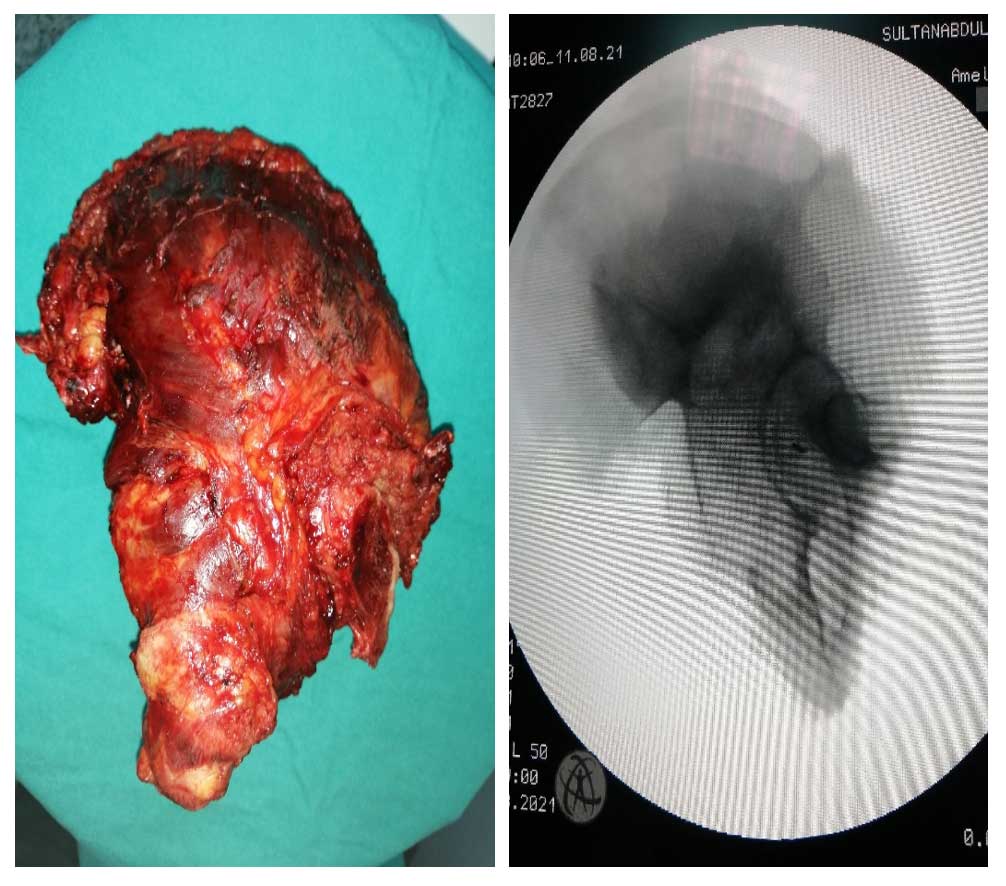

Ameliyat Esnası: Çıkarılan tümör dokusunun klinik ve skopi görüntüsü.